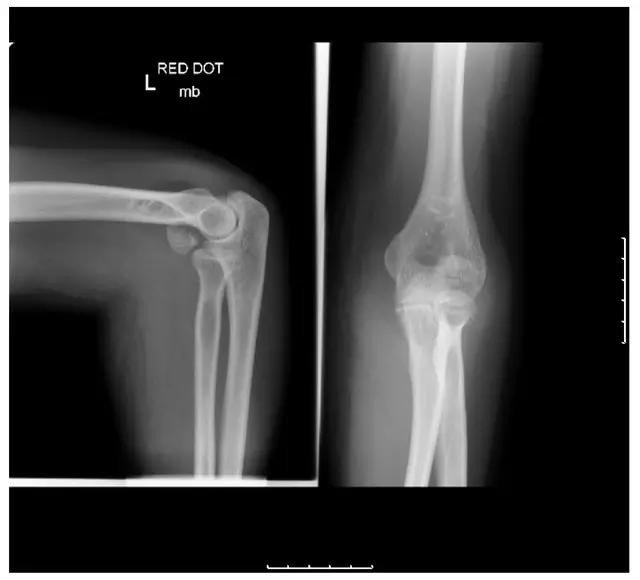

Kocher-Lorenz 骨折(来源:The often-missed Kocher-Lorenz elbow fracture. Revue de Chirurgie Orthopédique et Traumatologique, Volume 95, Issue 7, November 2009, Pages 658-661)

6. Hahn-steinthal 骨折

全肱骨小头骨折,为一种少见的关节内骨折,多见于成年人。常由于跌倒时手过度伸直或在屈肘时因桡骨小头撞击肱骨小头,并同时有外翻力存在时发病,亦可伴有滑车骨折与内侧副韧带的撕裂。X 线表现为全肱骨头骨折,向上移位。

Hahn-steinthal 骨折 X 片(来源:Hahn-Steinthal fracture: a case report.BioMed central Cases Journal20081:239)

Hahn-steinthal 骨折 CT 片(来源:Hahn-Steinthal fracture: a case report.BioMed central Cases Journal20081:239)